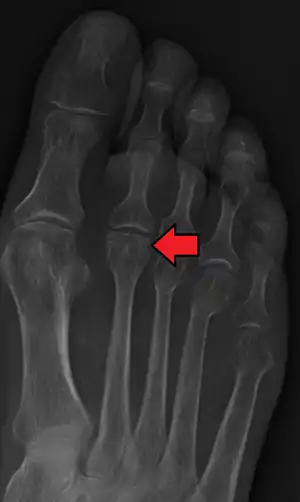

Freiberg disease

Freiberg disease, also known as a Freiberg infraction, is a form of avascular necrosis in the metatarsal bone of the foot. It generally develops in the second metatarsal, but can occur in any metatarsal. Physical stress causes multiple tiny fractures where the middle of the metatarsal meets the growth plate. These fractures impair blood flow to the end of the metatarsal resulting in the death of bone cells (osteonecrosis). It is an uncommon condition, occurring most often in young women, athletes, and those with abnormally long metatarsals. Approximately 80% of those diagnosed are women. [1]

| Freiberg disease as seen on plain film | |